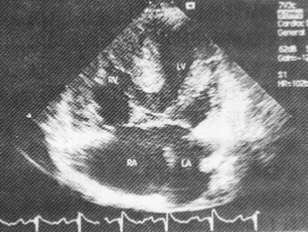

该病例心脏超声检查如图所示,最可能的诊断为

A.原发孔房间隔缺损

B.左心室右心房通道

C.完全型心内膜垫缺损

D.部分型心内膜垫缺损

E.混合型房间隔缺